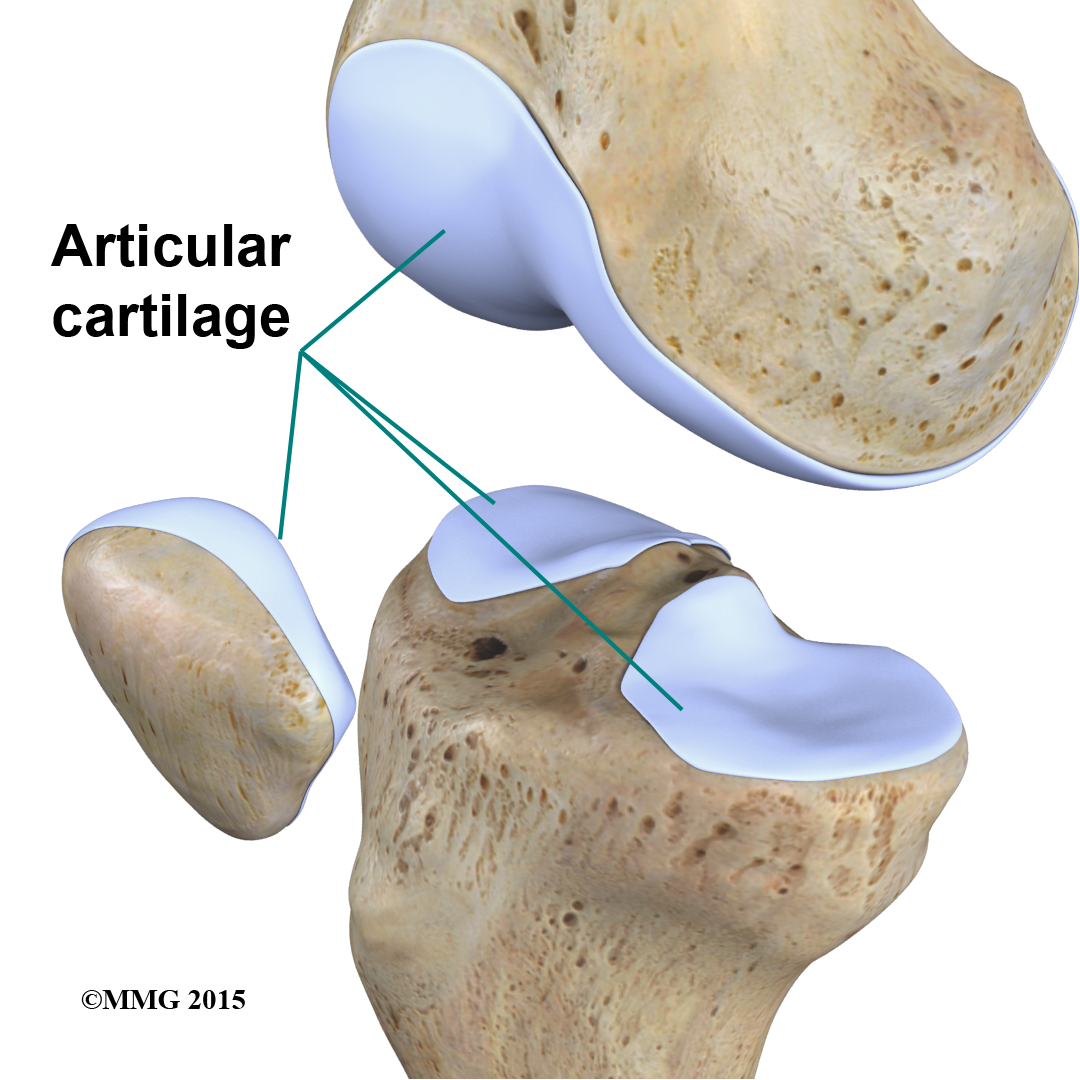

is the material that covers the ends of the bones of any joint. This material is about one-quarter of an inch thick in most large joints. It is white and shiny with a rubbery consistency. Articular cartilage is a slippery substance that allows the surfaces to slide against one another without damage to either surface. The function of articular cartilage is to absorb shock and provide an extremely smooth surface to facilitate motion. We have articular cartilage essentially everywhere that two bony surfaces move against one another, or articulate. In the knee, articular cartilage covers the ends of the femur, the top of the tibia, and the back of the patella.

Knee Articular Cartiliage

Without the menisci, any weight on the femur will be concentrated to one point on the tibia. But with the menisci, weight is spread out across the tibial surface. Weight distribution by the menisci is important because it protects the articular cartilage on the ends of the bones from excessive forces. Without the menisci, the concentration of force into a small area on the articular cartilage can damage the surface, leading to degeneration over time.

In addition to protecting the articular cartilage, the menisci help the ligaments with stability of the knee. The menisci make the knee joint more stable by acting like a wedge set against the bottom of a car tire. The menisci are thicker around the outside, and this thickness helps keep the round femur from rolling on the flat tibia. The menisci convert the tibial surface into a shallow socket. A socket is more stable and more efficient at transmitting the weight from the upper body than a round ball on a flat plate. The menisci enhance the stability of the knee and protect the articular cartilage from excessive concentration of force.